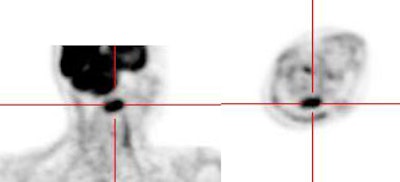

|

Head and neck activity: The images below show typical uptake in the tonsils (black arrows), submandibular glands (blue arrows), and parotid glands (red arrows) |